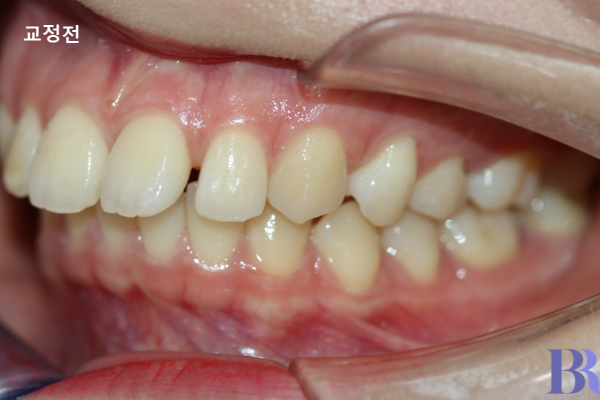

발치교정 사례 : 윗니와 아랫니 앞뒤 차이가 심하게 나네요.

편측 발치교정 : 윗니와 아랫니 앞뒤 차이가

정상적으로 줄어든 것을 확인할 수있다.

교정 전후 옆모습입니다.

윗니와 아랫니 앞뒤 차이가

정상적으로 줄어들었습니다.

교합도 긴밀하게 잘 맞아들어

가는 것을 볼 수 있습니다.